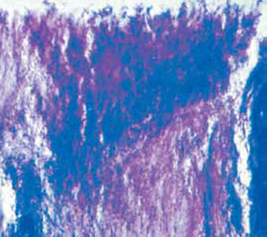

Varios productos similares al Novamin® han sido aprobados por la FDA☆ como agentes desensibilizantes como son el Sootherx®, Oravive®, Nucare®, Renew®, Durashield® y Vitalmin®. La evidencia demostrada es un bloqueo rápido y completo de los túbulos dentinarios expuestos para ser aplicado también en los casos de erosión, ya que una precipitación de cristales en estas zonas es benéfica si se modifica también su causa. El calcio y fosfato adicionados son útiles en la remineralización si se cuenta con un sistema apropiado para proporcionarlo y precipitarlo, condicionado a una frecuencia adecuada, ya que un factor adverso como un exceso de calcio que bloquee la superficie del esmalte impedirá entonces la remineralización de la zona más profunda.24En lo que se refiere a la placa dentobacteriana, ahora reconocida como una biopelícula, hay también conocimientos innovadores. Mencionaremos que actualmente, ya no se estudian los microorganismos que la componen por separado, sino en su conjunto, entendiendo así mejor su formación, estructura y comportamiento (Figuras 4 y 5).

Después del advenimiento del microscopio electrónico, la biopelícula (BP) ha sido comprendida y estudiada en forma diferente. Lejos de considerarse un conglomerado de bacterias, hoy se sabe, tiene una organización «inteligente» donde existe comunicación entre los microorganismos que la componen y forman entre otras cosas canales para la circulación tanto de nutrientes como para sus desechos.25),(26

La formación de ésta se inicia cuando las bacterias se adhieren a una superficie en una solución acuosa, en casi cualquier material como tuberías, metal, plástico, piedras, implantes, prótesis y dientes. Esta biopelícula se compone de muchas especies de bacterias, hongos, algas, protozoarios, detritos y elementos de corrosión. Una vez adherida, los microorganismos causan diversas alteraciones, dependiendo del medio ambiente y la resistencia del huésped.